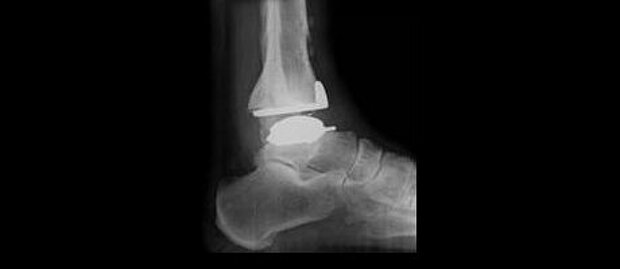

Beim Verbindungsgelenk zwischen Fuß und Unterschenkel können Beschwerden mittels Operation oder auch teilweisem Gelenkersatz gemindert werden.

- Prothetik oberes Sprunggelenk